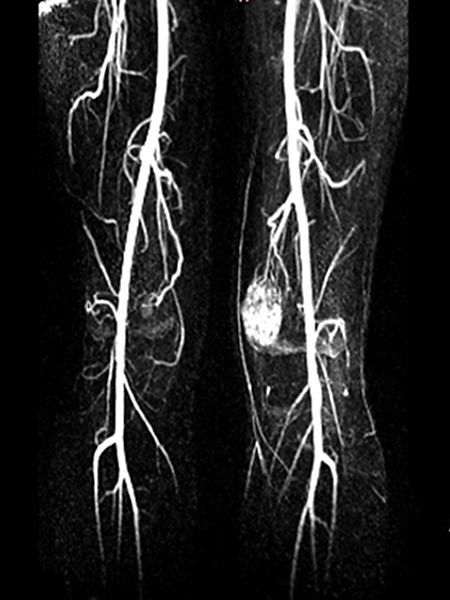

In coronal T2-weighted, fat-suppressed MRI, the extent of the strongly hyperintense venous malformation in the cranio-caudal direction is delineated.

Dynamic contrast-enhanced MR angiography in an early, arterial phase shows early enhancement with arterial vascularization of the venous malformation. This indicates arteriovenous fistulas in the venous malformation.